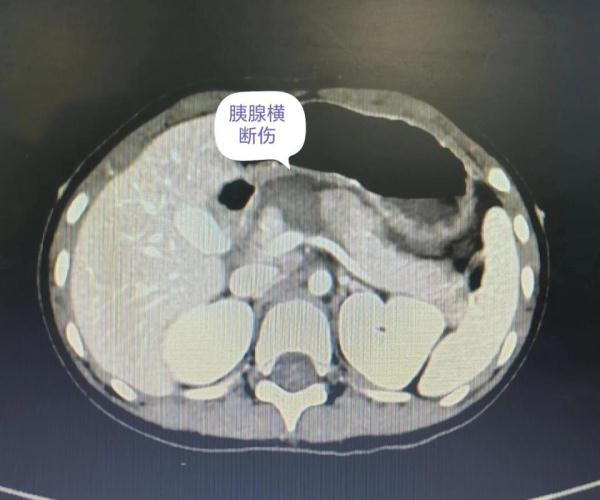

小洁入院后,儿童重症医学科立即开展诊疗工作。禁食、补液,急诊完善检查,请会诊等。孩子腹部CT提示胰腺横断伤、主胰管断裂,胰液渗入了腹腔,持续进展随时可危及生命。更为关键的是,胰腺损伤可导致组织坏死,手术难度大,更难的是如何保护孩子的胰腺功能,以防在其成长过程中出现代谢问题。

儿童重症医学科立即请肝胆外科李国光主任医师会诊,李国光主任医师团队紧急进行病情讨论,制定急诊手术方案。一切准备就绪后,手术团队为小洁进行了开腹手术,术中对创伤性坏死性胰腺炎进行清创,切除胰腺坏死部分,并进行了胰头残端封闭及胰尾部空肠R-Y吻合术。经过5个小时,手术成功,术后小洁回到儿童重症医学科,经抗感染、疼痛、营养等一系列管理,病情很快好转,腹膜炎得到控制,没有出血、腹胀等情况,肠道通畅,胰腺功能得以保留。术后不到5天,孩子已经神采奕奕,可以愉快地进食,还会开心地和医护人员聊动画片。7月31日,小洁顺利出院了。